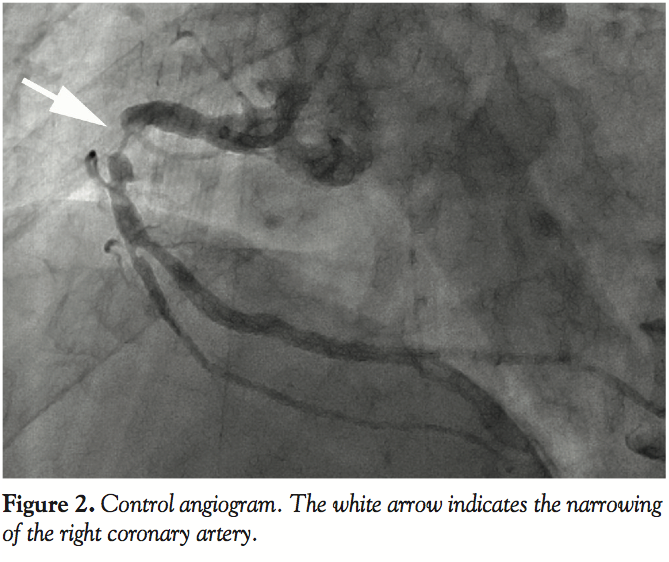

Case Report. A 64-year-old man was referred to our hospital with exertional chest pain. An angiogram showed severe narrowing of the proximal RCA (Figure 2). We decided to perform PCI, and the patient was administered antiplatelet agents. A 6 French (Fr) guide catheter (JR 4.0) was advanced into the RCA via the right radial artery. A 0.014˝ guidewire easily passed through the narrowed artery and entered the atrioventricular (AV) branch. IVUS was performed to evaluate the plaque characteristics. The IVUS catheter passed through the lesion with some difficulty.